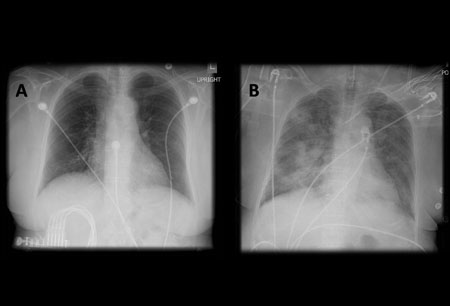

A. Radiografía portátil de tórax en posición erguida antes de la aspiración; B. Radiografía de tórax 1 hora después de la aspiración, en la que se muestran infiltrados alveolares difusos bilaterales, peores en las bases del lado derecho

De la colección del Dr. Henri Colt